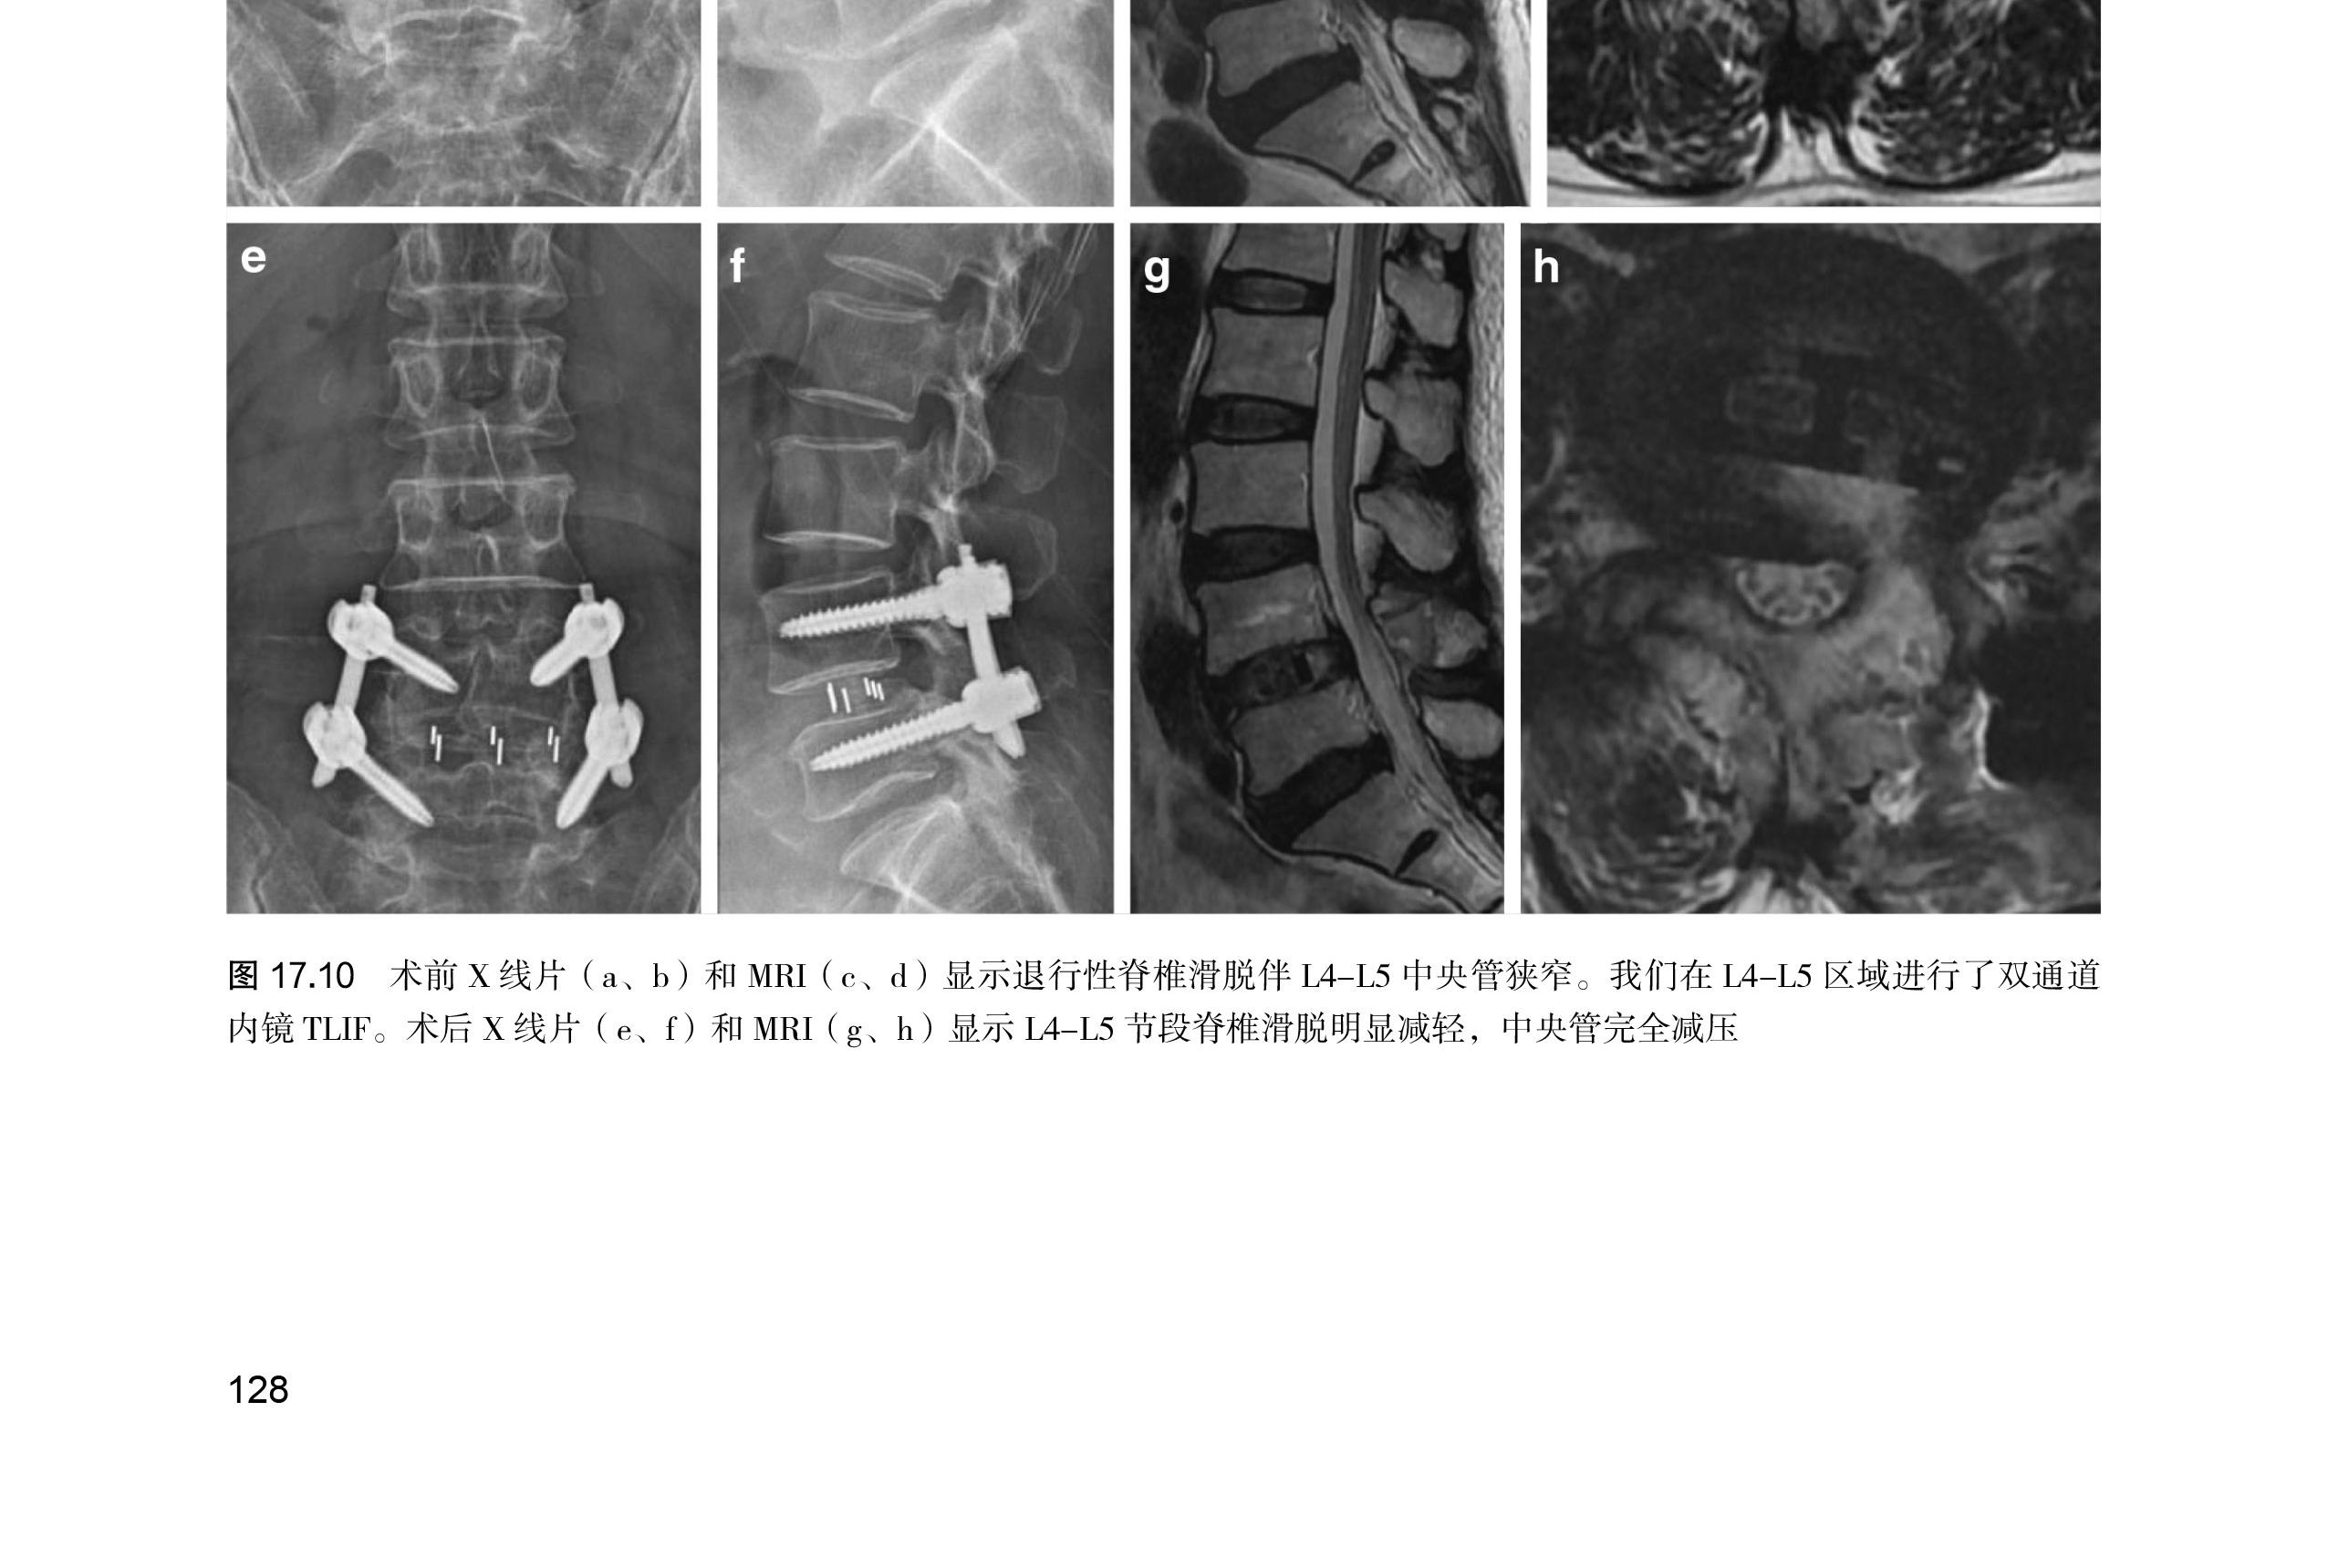

第 17 章 双通道内镜腰椎间融合术 …… 123